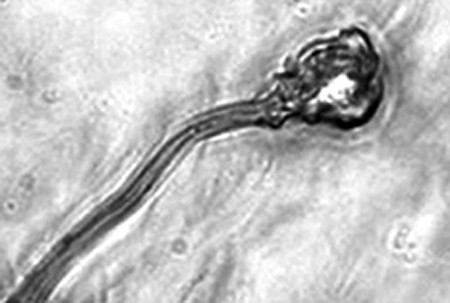

據(jù)報告的主要作者卡里姆教授介紹,這種試管培育精子(IVDsperm)與人類自然產(chǎn)生的精子并不完全一樣,但兩者擁有4個重要的相似點:它們包含有23個染色體;有精子那樣的頭和尾巴;有可以使卵細(xì)胞受精的蛋白質(zhì);它們也可以像天然精子一樣游動。